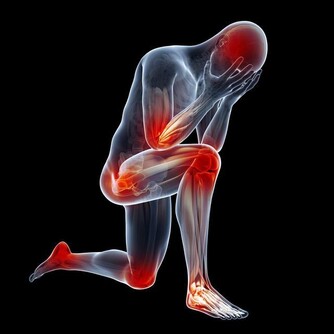

人老腿先知,腿部的衰老很早就可能表現出來,專家提醒說,如果出現以下情況,就要引起注意了:

腿腳沒有原先靈便了。這是衰老的最早特徵。40歲後,很多人感到腿腳不靈活,稍微多走點路,就像腿上灌滿鉛,發酸發脹,上樓梯也越來越費勁,沒爬幾層就氣喘吁籲。

幹點活就腰酸腿疼。特別是中年女性,只要站的時間一長,就會覺得腰酸腿痛。

咳嗽時,腿還會出現放射性疼痛。如果小腿肚出現壓痛更要注意,說明腸胃已經開始“罷工”了。

走路變慢。不知不覺中,步速越來越慢。偶爾走快點,會覺得腿腳不聽使喚,過後會連續酸痛好多天,甚至出現肌肉萎縮的情況。

雙腿一側發涼。即使夏天也總感到小腿肚涼颼颼的,有時還覺得從臀部開始,到腳後跟,中間一條線都涼涼的。

這可能是血液循環不暢造成的,也可能和腰椎間盤病變有關。

抽筋次數增多。如果不是在運動後或因為受涼而抽筋,那就要注意了,這可能是骨質疏鬆的表現。

有些人還會出現足跟疼痛,也必須引起注意。

腫脹。血液循環不好會導致腿脹,同時這也是心腦血管病或腎臟疾病患者常有的症狀。

靜脈曲張。女性更容易出現這種情況,20歲後就有可能發生。一旦腿上的血管突然非常清晰,彎彎曲曲像蛇一樣,說明腿部血管出現了勞損。

髖膝關節疼痛。幾乎所有關節都會隨著年紀增大而變得脆弱,特別是髖、膝這兩處關節。如果你發現在下樓梯、蹲下或跳躍時出現不適,甚至腿部有摩擦磨損、卡住動不了的感覺,說明關節已經急需保護了。